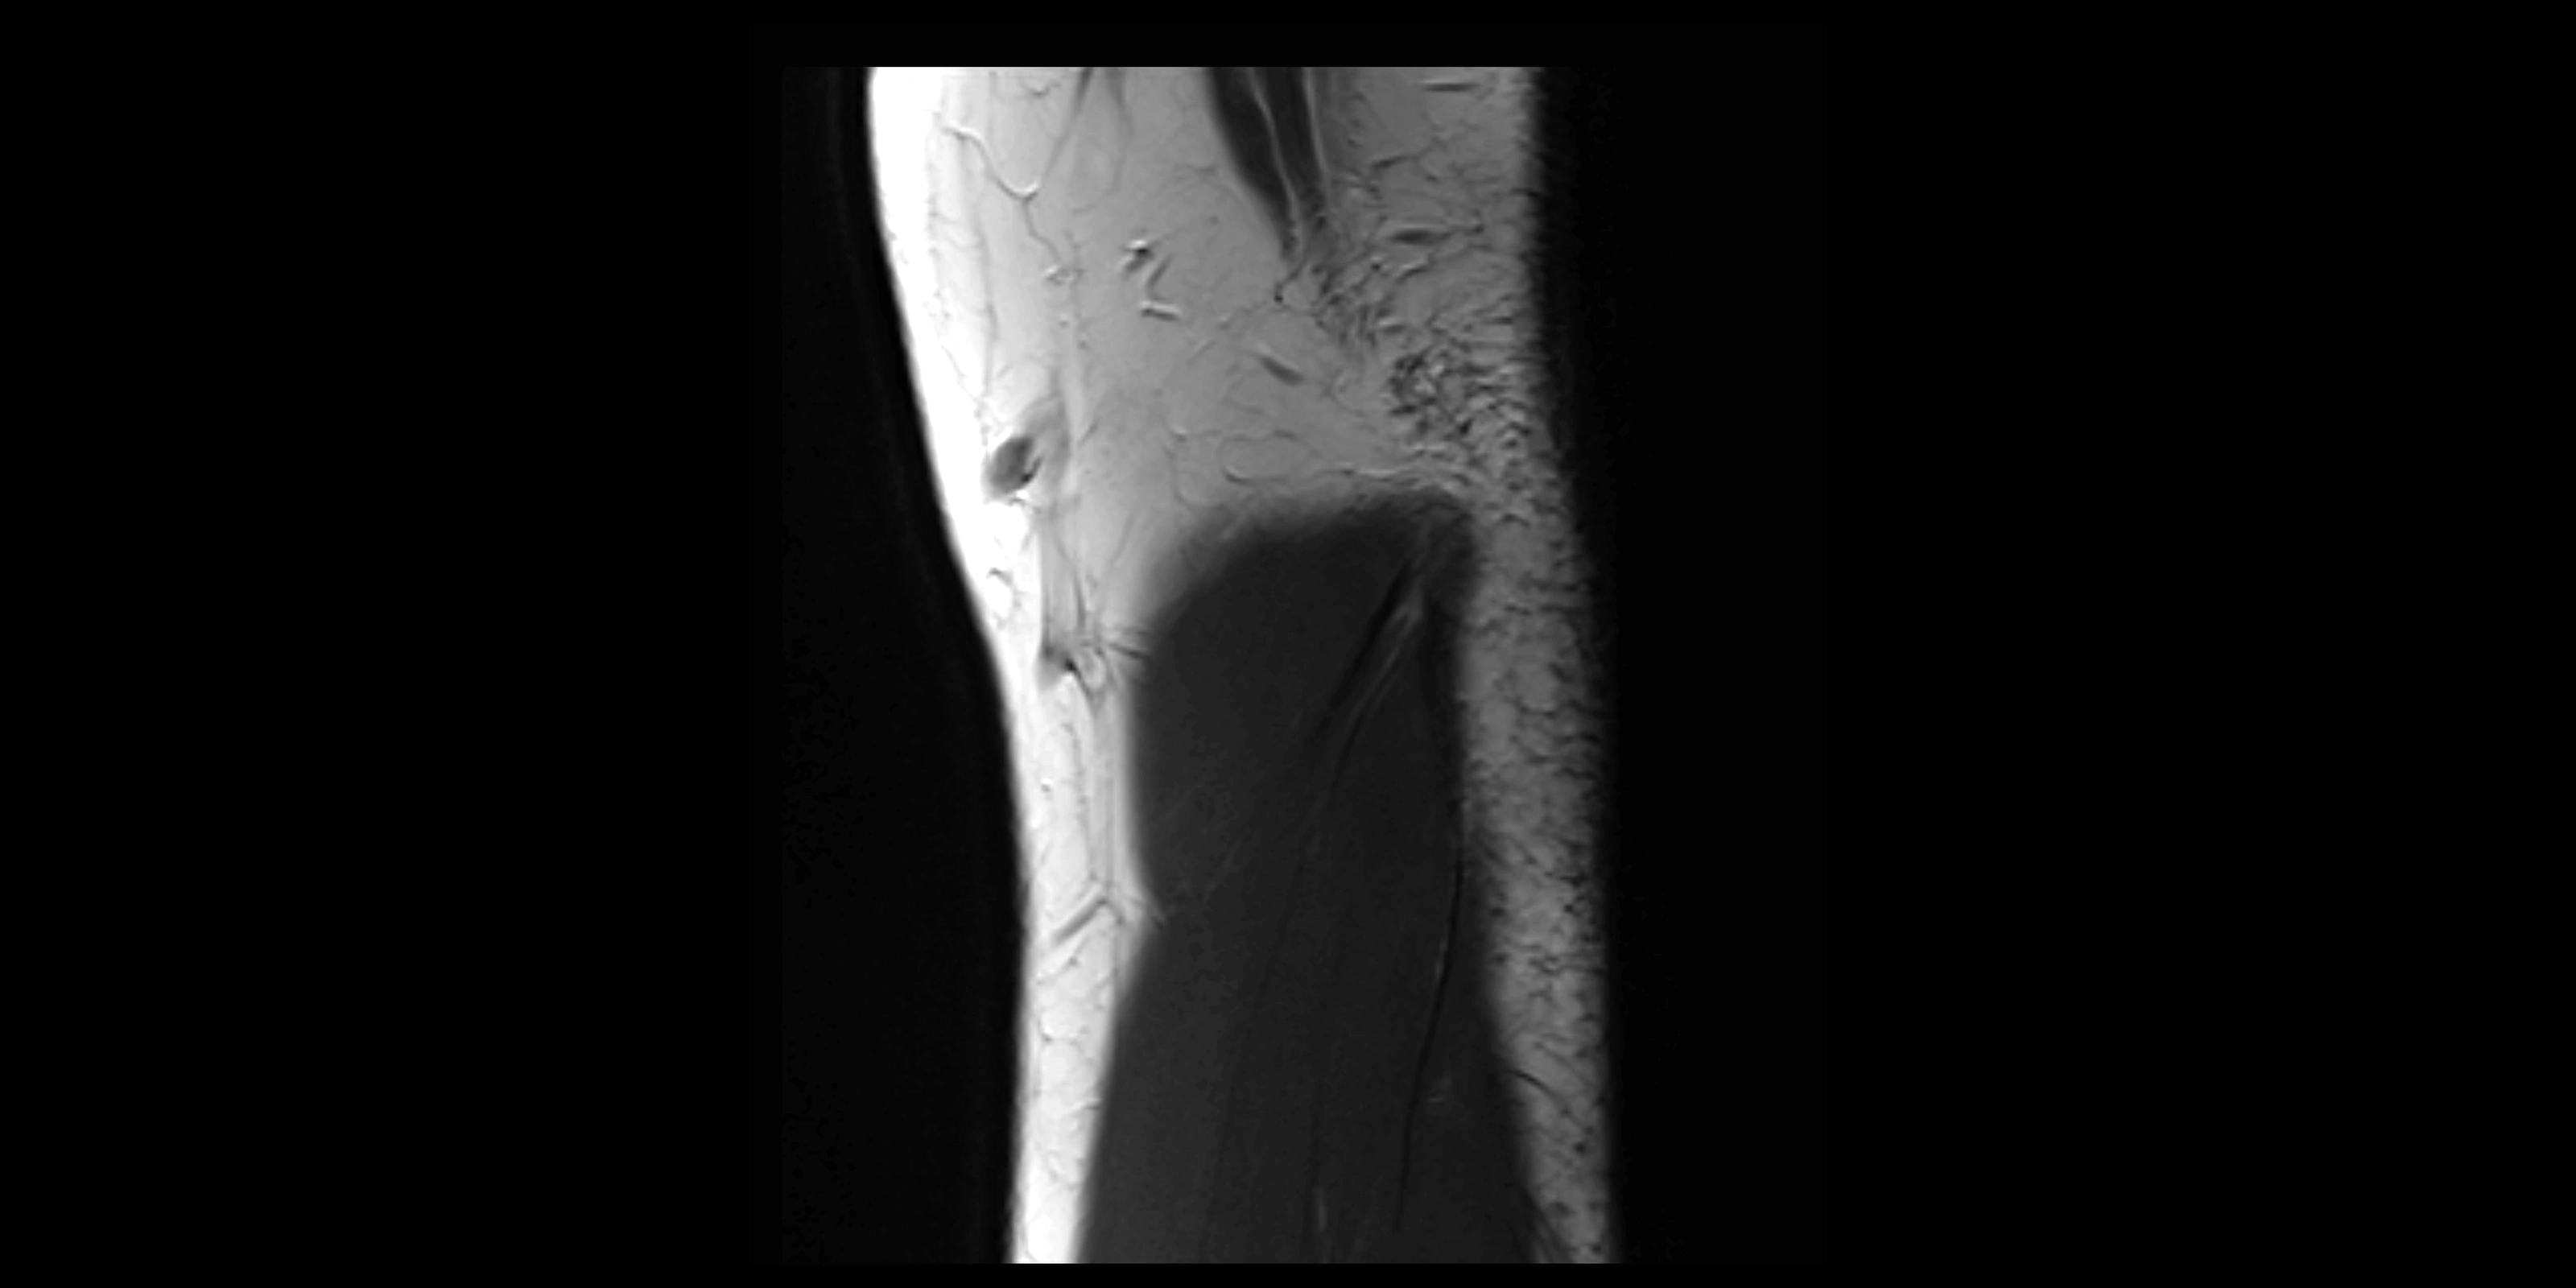

Fullscreen Image